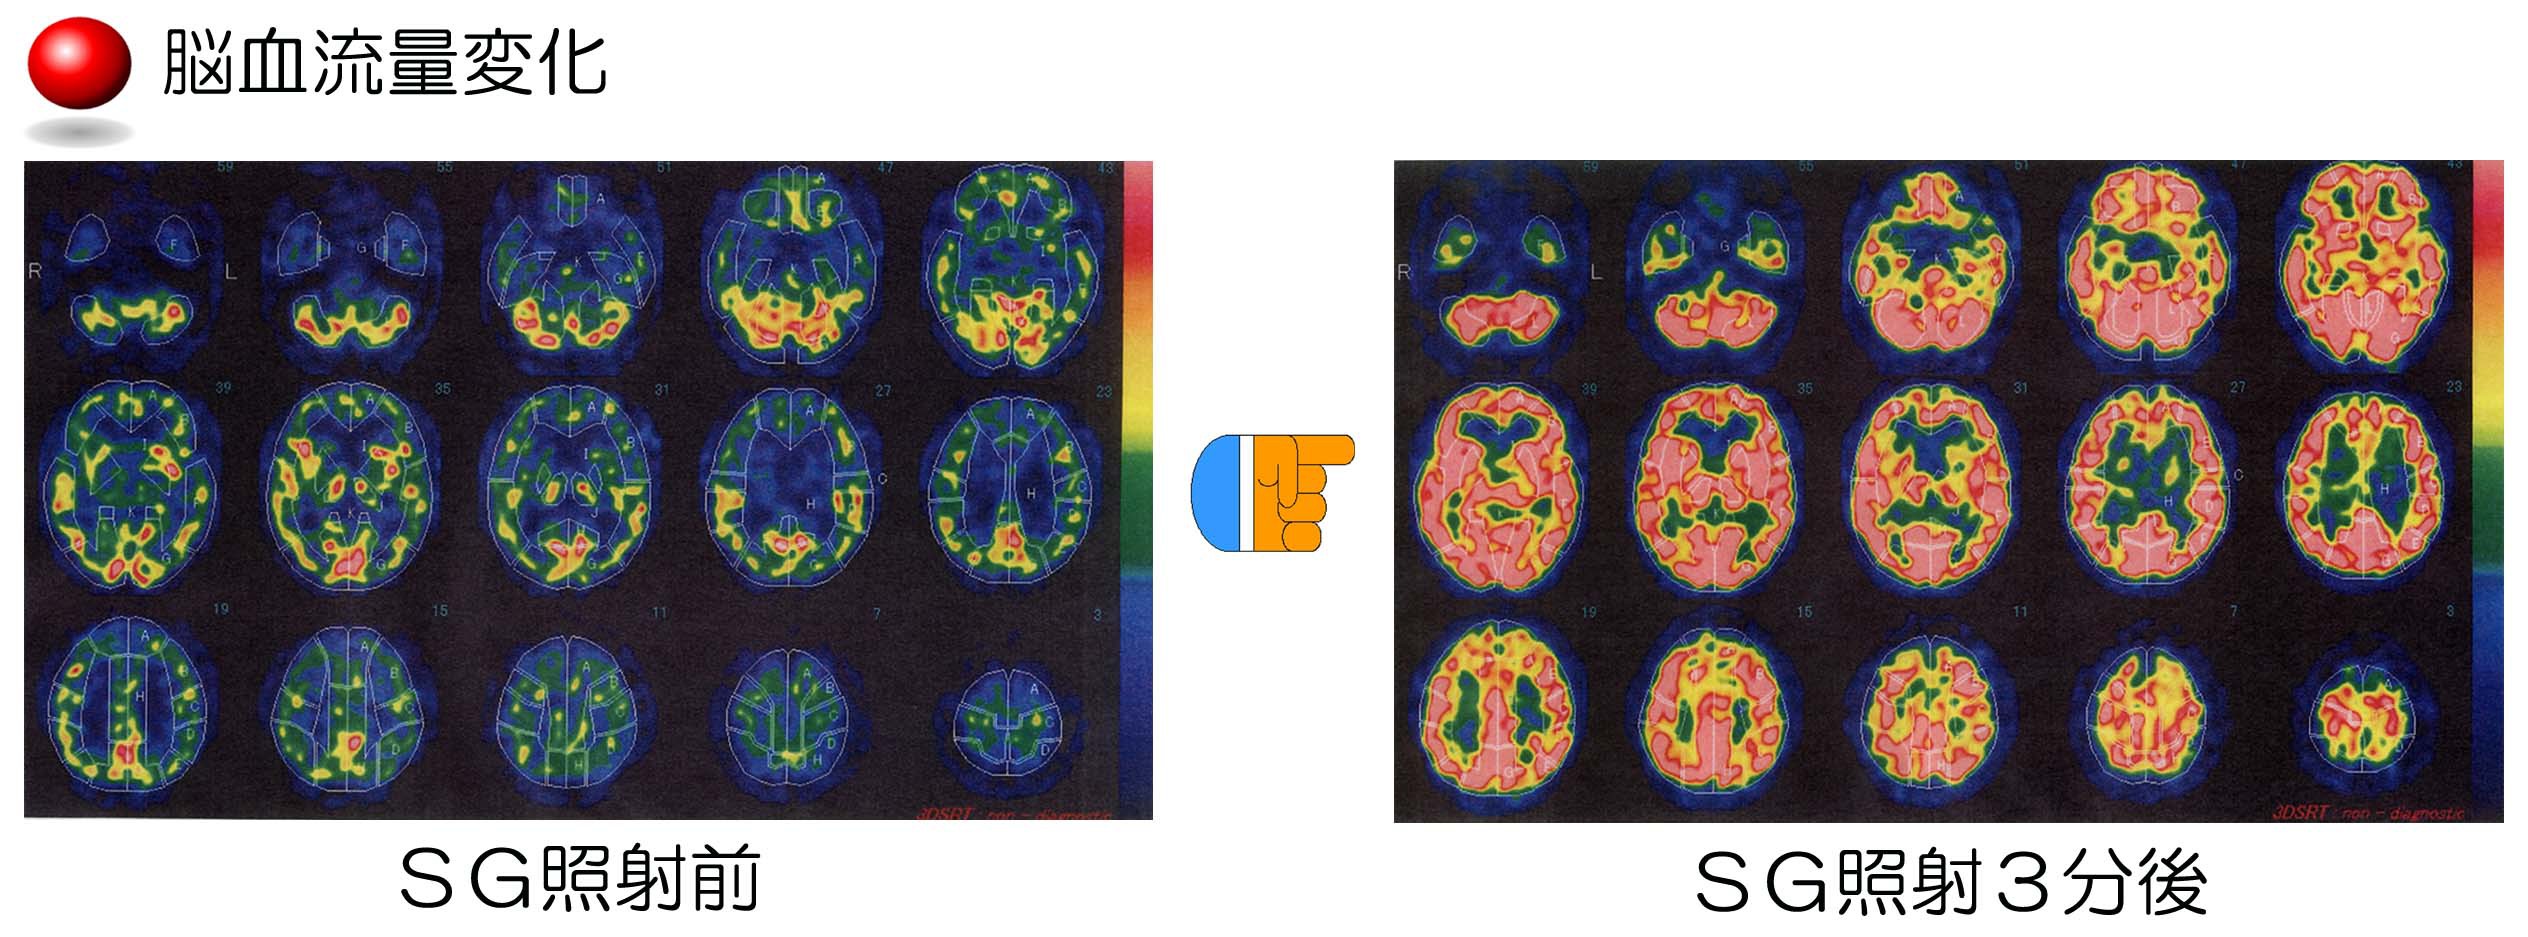

【星状神経節近傍照射療法】

星状神経節への近傍照射は、どのような患者様にも施行でき、無痛かつ無侵襲であることに加えて、実施が容易な治療法です。ストレス等で緊張している交感神経を正常な状態に戻し、血行を改善することにより、多くの疾患に効果を発揮します。